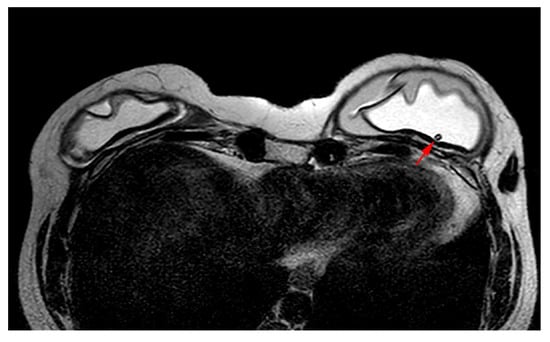

- Sharma, B.; Jurgensen-Rauch, A.; Pace, E.; Attygalle, A.D.; Sharma, R.; Bommier, C.; Wotherspoon, A.C.; Sharma, S.; Iyengar, S.; El-Sharkawi, D. Breast Implant-associated Anaplastic Large Cell Lymphoma: Review and Multiparametric Imaging Paradigms. Radiographics 2020, 40, 609–628. [Google Scholar] [CrossRef] [PubMed]

- Adrada, B.E.; Miranda, R.N.; Rauch, G.M.; Arribas, E.; Kanagal-Shamanna, R.; Clemens, M.W.; Fanale, M.; Haideri, N.; Mustafa, E.; Larrinaga, J.; et al. Breast implant-associated anaplastic large cell lymphoma: Sensitivity, specificity, and findings of imaging studies in 44 patients. Breast Cancer Res. Treat. 2014, 147, 1–14. [Google Scholar] [CrossRef] [PubMed]

- Rotili, A.; Ferrari, F.; Nicosia, L.; Pesapane, F.; Tabanelli, V.; Fiori, S.; Vanazzi, A.; Meneghetti, L.; Abbate, F.; Latronico, A.; et al. MRI features of breast implant-associated anaplastic large cell lymphoma. Br. J. Radiol. 2021, 94, 20210093. [Google Scholar] [CrossRef]